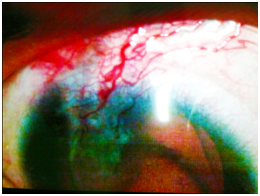

On examination, the ophthalmologist detected severe conjunctival chemosis, corneal edema, and vertical linear corneal laceration (Figure 1) extending from 12 o’clock towards 5 o’clock with possible extension to the sclera, iris prolapse, total hyphema and subconjunctival hemorrhage. Posterior segment could not be examined. Review of systems was totally free. A protective eye shield was placed and the patient was sent for CT scan axial and coronal sections which revealed periorbital swelling but no intraocular or intraorbital FB or intraocular hemorrhage no injury to orbital walls or extraocular muscles. The patient then was given tetanus immunization, antiemetics, analgesics and intravenous broad spectrum antibiotics and prepared for globe rupture repair under GA. Laboratory tests included a full blood count, liver function tests, INR, prothrombin time, partial thromboplastin time, kidney function tests, all were within normal.

Figure 1 Repair of corneal laceration and application of therapeutic contact lens.

Repair of the right globe rupture was done under GA, which included sterilization of conjunctiva by povidone iodine eye drops, No scleral extension of the wound was found. Limbal sutures were placed using 10/0 Nylon sutures. The prolapsed iris was viable and was reposited by iris spatula. Corneal wound was sutured by 10/0 Nylon sutures. Hyphema was washed using bimanual irrigation aspiration technique. Traumatic cataract was detected and lensectomy was performed. Anterior vitrectomy was done through pars plana incision which was sutured at the end of operation using 8/0 virgin silk sutures. Anterior chamber was reformed by viscoelastic solution and the patient was left aphakic. Side ports were sutured and a therapeutic contact lens was applied.